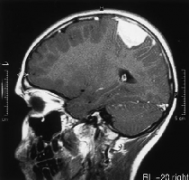

脑膜瘤 是一种常见的脑瘤,它在脑膜(覆盖和保护大脑和脊髓的区域)中缓慢发展。大多数脑膜瘤是良性的,在大小和位置上差异很大。脑膜瘤严重吗?几乎...

脑膜瘤 是由覆盖大脑和脊髓的膜(脑膜)发展而来的脑瘤。它们是成人较常见的原发性脑瘤。大多数脑膜瘤(85- 90%)属于良性肿瘤,其余10- 15%属于非典型或恶性...

脑膜瘤是较常见的中枢神经系统原发肿瘤之一,国际卫生组织(WHO) (2016)将其定义为:“一组大多为良性、生长缓慢的肿瘤,较有可能来源于蛛网膜层的脑膜上...

脑膜瘤是良性还是恶性?脑膜瘤是较常见的原发性中枢神经系统肿瘤,约占三分之一。脑膜瘤是一种起源于蛛网膜帽状细胞的中枢神经系统肿瘤。脑膜瘤约占...